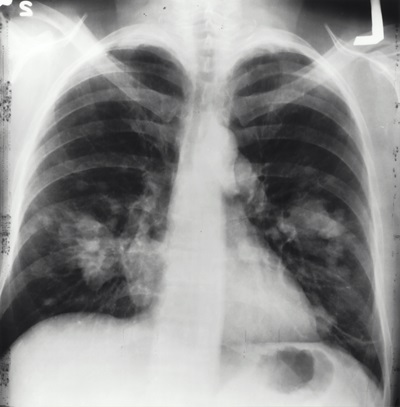

直至第六次求診,黃醫生才安排胸部X光檢查。放射科報告顯示左肺有「微小陰影」,結論為「可能屬良性瘢痕或輕微感染」,建議十二個月後覆查。黃醫生雖向陳先生轉達結果,但未建議進一步檢查。

十二個月後,陳先生工作期間突然昏倒,送公立醫院急症室後,經CT掃描及活檢確診三期肺癌,並已擴散至骨骼。腫瘤科醫生指出,腫瘤很可能已存在逾一年,診斷延誤令陳先生錯失早期治療良機,大大減低治瘉機會。